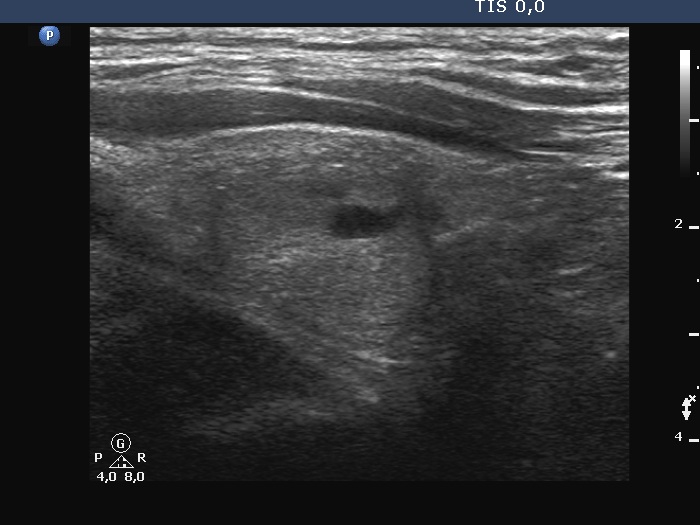

Examination a year after the first visit (third row of images):

Clinical presentation: The patient had no complaints.

Palpation: no abnormality.

Laboratory tests: TSH 1.60 mIU/L, FT4 15.6 pM/L, aTPO 12 U/mL.

Ultrasonography: The dorsal part of the right lobe remained hypoechoic. The nodule in the left lobe has increased in size and presented halo and signs of perinodular vascularity.

Cytology of the nodule resulted in benign lesion.

Suggestion: repeat examination in three years.

Comment. In the active phase of subacute thyroiditis, a nodule can be obscured. The real structure of the thyroid can be revealed only when the hypoechogenicity disappears or decreases significantly.